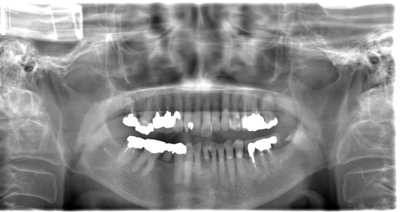

CASE 2

基本情報

| 年齢・性別 | 30代・男性 |

| 主訴 | 左上下親知らず抜きたい |

| 抜歯期間 | 30分 |

| 抜歯費用 | 約2,500円(保険内) 別途CT撮影で3,000円 |

| 抜歯内容 | 左上下の親知らず抜歯 |